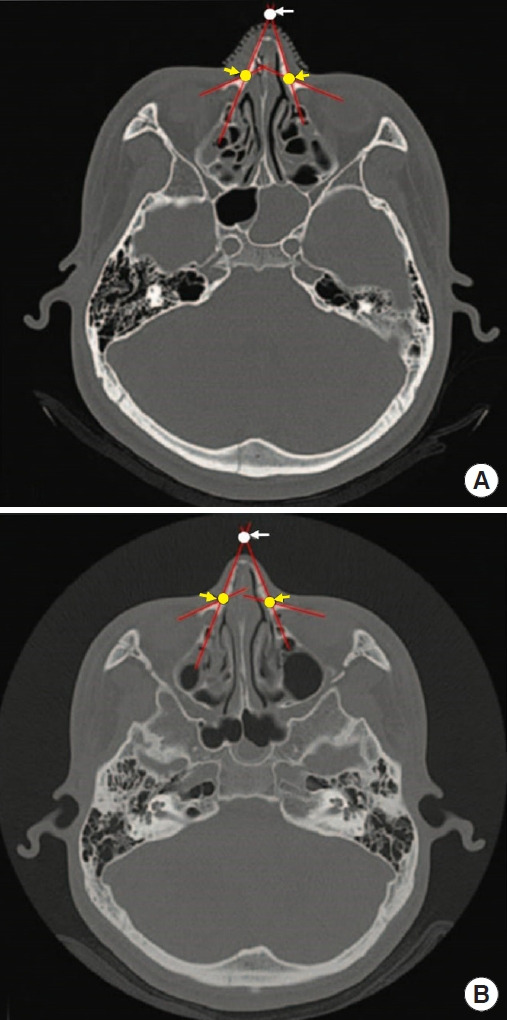

Methods: We conducted a retrospective study comparing cases of simple fractures classified as type II-III according to Higuera's classification that were treated surgically with closed reduction. Patients were divided into two groups: the control group (no packing, no K-wire splint) and the experimental group (no packing with K-wire splint). We calculated the difference in the distance (mm) between the centerline of the triangle and the apex on facial bone on computed tomography scans immediately after surgery and at a mean of 3.6 months after surgery, assessing postoperative symptoms at 3 days after surgery.

Results: The experimental group (no packing with K-wire splint) showed no statistically significant difference in radiological outcomes compared to the control group. The distance from the apex to the centerline of the triangle was 0.009± 0.012 mm in the control group and 0.008± 0.009 mm in the experimental group. However, the control group reported fewer postoperative symptoms, including nasal obstruction and dry mouth.